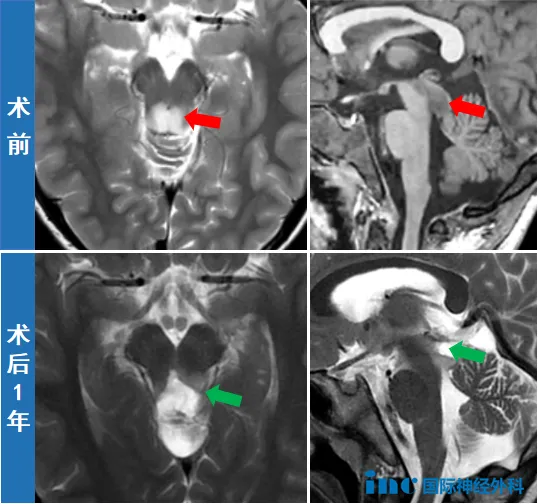

该异常信号位于脑干中脑背侧,初步怀疑为胶质瘤。此时家属才意识到,孩子之前出现的头痛、呕吐等症状并非单纯由感冒引起。为明确诊断,一家人带晓飞前往北京进一步就诊,CT和MRI检查再次确认中脑顶盖存在占位性病变,大小约为18×12×14毫米,边界不清晰,医生怀疑为低级别胶质瘤。

数日后,适逢巴教授来华进行手术示范,晓飞成为当期接受治疗的患者之一。手术室内,微光亮起,仿佛照亮了男孩的求生之路。在巴教授主刀下,手术顺利实施,肿瘤被成功切除。术后病理报告显示为低级别神经上皮肿瘤,此类肿瘤通常预后良好。

术后第二天,巴教授前来查房,躺在病床上的晓飞睁大双眼,在教授指导下活动眼球、手臂和双腿,均未见异常。这场惊心动魄的手术未对年幼的孩子造成任何神经功能损伤,晓飞已成功通过生命考验,迎来平安成长的机会。